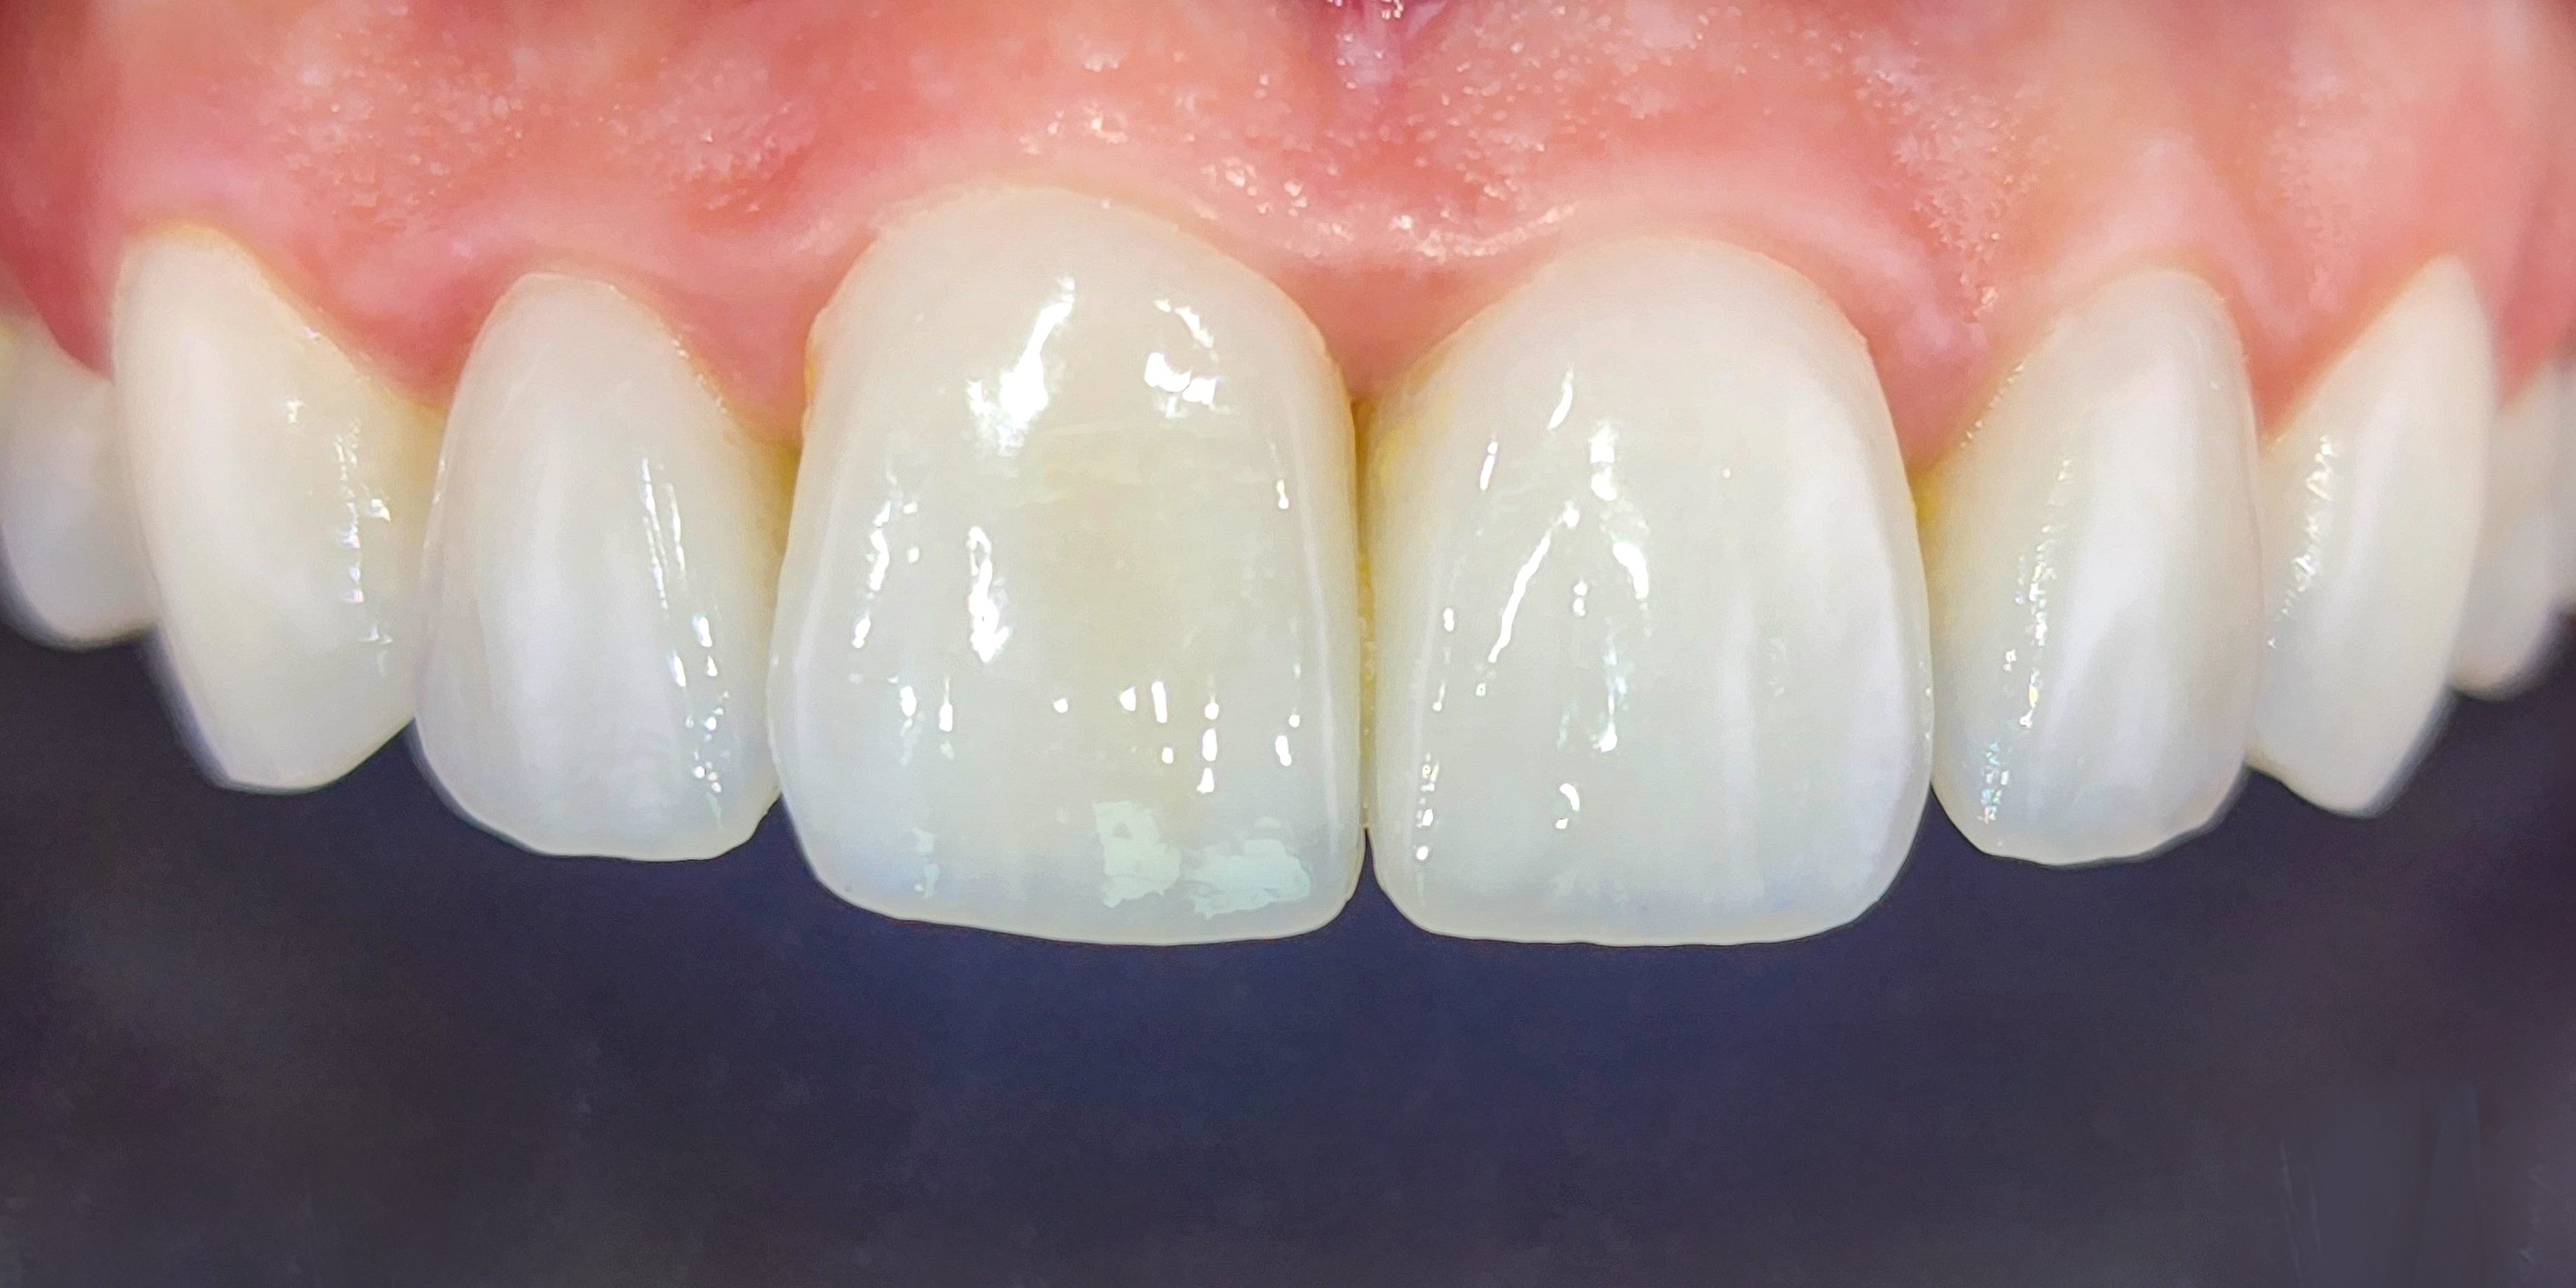

Bonding porcelain veneers, or as they go by their foreign name – laminate veneers, requires a lot of technical and medical skill, a lot of experience, perfectionism and an artistic eye. The transition area between the veneers and the gums is where millions of bacteria accumulate, causing gingivitis, bleedings and pain. The gums look swollen and unsightly. It is imperative to maintain good gum health to get a natural-looking and beautiful result. The goal is to achieve a beautiful and glamorous smile without letting others see that we have applied porcelain veneers. That is why one must not compromise when choosing a dentist.A cost-based compromise almost always leads to double work and double costs. The first time, people pay a low price, and the second time, they pay the right price to replace the porcelain veneers. A natural, healthy, white and beautiful smile is Dr. Gilad Fiskus’s signature.